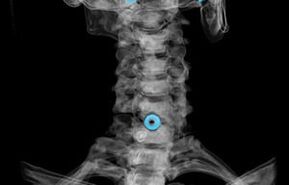

- Durchführung eines X -RAY: Diese Methode bestimmt die Veränderung der Mobilität und Anordnung der Wirbel, liefert eine Untersuchung einer Abnahme der Bandrisse und ermöglicht es, Salzablagerungen zu sehen

Es wird angenommen, dass es für eine genaue Diagnose genügend Inspektionsdaten und X -Ray gibt. Die verbleibenden Optionen werden nur in Fällen verwendet, in denen die Situation nicht klar ist und es einen Platz für Zweifel gibt.